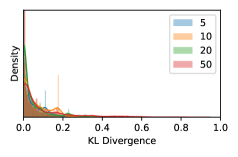

5.1 Distribution of Uncertainty Scores

Distribution of Uncertainty Scores Across Different Severity Levels As explained in Section 3, each uncertainty metric essentially defines an order/ranking among the data points. We conducted an analysis to better understand what data will be assigned high uncertainty under a particular uncertainty metric . Picking out the highest ranked data points (), we calculated the ratio of data points from each SL. Figure 4 summarizes the results as box plots for the Kaggle-DR and the Messidor-2 datasets; additional detailed statistics can be found in Table S.1 in the supplementary materials. From the plot and table, SL1 & SL2 examples account for a higher proportion among the top-ranked uncertain examples across the three ensemble methods. This finding matches our intuition that incipient disease examples (SL1 & SL2) are more likely to be considered uncertain by ensemble methods due to their ambiguity.

In contrast, the MC-dropout method showed the worst overall performance among the three, as it can be seen from the high ratios of SL0 examples among the uncertain negatives in Figure 4. The histograms in Figure 2 provides another perspective to look into the phenomenon, where a decent proportion of MC-dropout model’s predictions on SL0 inputs entailed low confidence (far from 0 or 1), which from another angle explained why MC-dropout was less specific in terms of lower FNP; many no-DR inputs (i.e. SL0) were erroneously assigned high uncertainty by MC-dropout models.

As discussed in Section 5.1 and Section 5.3 in the main paper, the mean metric and the stacking ensemble will have better performance in the precision (specificity) on the ambiguous data. Here, more detailed results are shown in Figures S.3 & S.6 and Table S.1. Figures S.3 & S.4 show the histograms of the uncertainty score for Kaggle-DR and Messidor-2 datasets that are the in-distribution (i.d.) dataset in our experiment and FigureS.5 & S.6 show the histograms for ImageNet and CIFAR-10 datasets, which is the o.o.d. datasets in our experiment. Each group of histograms contains results from the three evaluated ensemble methods (stacking ensemble, MC-dropout and TTA) and the three uncertainty metrics (mean, var and kl). Additional detailed results not displayed in Figure 4 can be found in Table S.1, which shows the proportion of the data of different SLs varies across different . For comparison, we also included in Table S.1 the results from single learners, and the proportions of data of different SLs (before any selection was made).